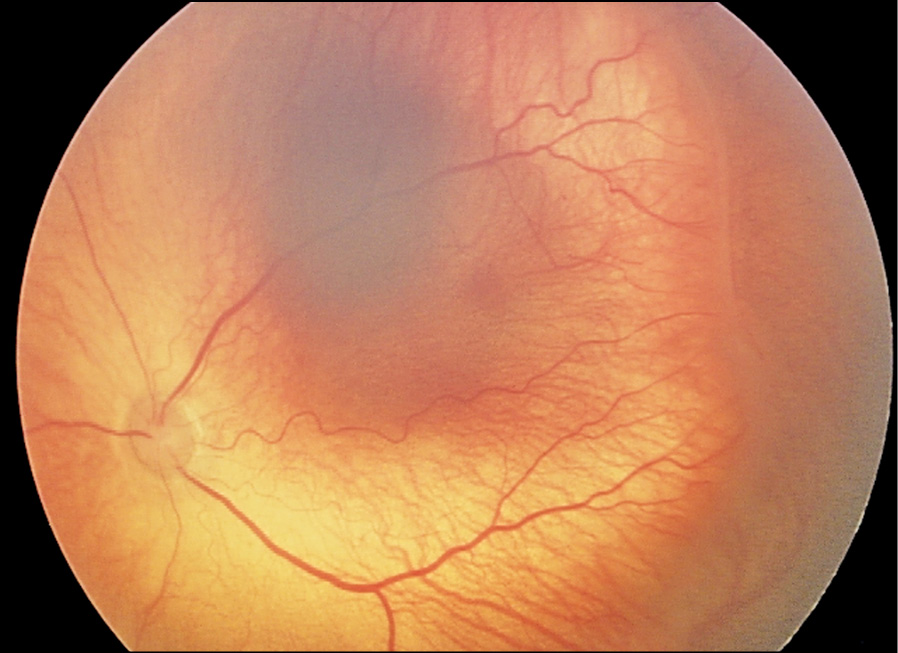

Клинический случай 1. Недоношенный мальчик, рождённый на 29-й недели гестации в результате экстракорпорального оплодотворения, из двойни, с массой тела 1350 г. Находился на лечении и выхаживании в СПб ГБУЗ «ДГБ №1» (в 2019 г. переименована в СПБ ГБУЗ «Детский городской многопрофильный клинический специализированный центр высоких медицинских технологий»). Первичный офтальмологический скрининг с помощью педиатрической ретинальной камеры «RetCam3» (США) проведён при достижении ребёнком 31-й недели постконцептуального возраста (ПКВ). При этом выявлены признаки незавершённости васкуляризации сетчатки на крайней периферии обоих глаз. В процессе регулярного мониторинга за состоянием глазного дна была диагностирована активная РН 2-й стадии с локализацией в зоне II сетчатки (рис. 1). К 36-й неделе ПКВ прогрессирование заболевания достигло порога (стадия 3, «плюс-болезнь»), что потребовало лазерного хирургического лечения. Для проведения лазерной коагуляции аваскулярных зон сетчатки использовали диодный лазер с длиной волны 532 нм (Iridex, США) и транспупиллярный доступ. После выписки из стационара было продолжено динамическое наблюдение офтальмологом в кабинете катамнеза амбулаторно-поликлинического отделения данного учреждения, где у пациента в 38 недель постконцептуального возраста зарегистрирован и документирован индуцированный регресс РН (рис. 2). Следующий осмотр состоялся через 2 недели (ПКВ — 40 недель), во время которого был обнаружен очаг опухоли в макулярной области сетчатки (рис. 3). Так как результаты всех обследований глазного дна с помощью RetCam регистрировались и архивировались в базе данных пациента, ретроспективный анализ ранее выполненного изображения показал наличие точечного очага опухоли, расположенного в центре макулы левого глаза (рис. 2), который корректно не интерпретировали, сосредоточив внимание на клинической картине РН. Несмотря на сверхмалый размер очага данный случай РБ относится к группе В исходя из его локализации.

Рис. 2. Индуцированный (после лазерной коагуляции сетчатки) регресс РН.

Fig. 2. Induced (after laser coagulation of the retina) regression ROP.